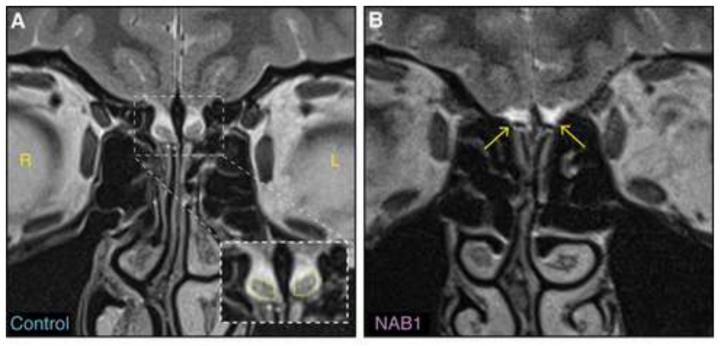

The new findings were unexpected: Drs. Tali Weiss and Sagit Shushan in the lab of Prof. Noam Sobel of the Institute's Neurobiology Department were conducting MRI scans of subject's brains in the Azrieli National Institute for Human Brain Imaging and Research on campus. One of the subjects, who had stated her sense of smell was normal, was found to be lacking olfactory bulbs in her brain. The subject insisted: Her sense of smell was not only normal, it was excellent. "We tested her smelling faculties in every way would could think of, and she was right," says Sobel. "Her sense of smell was indeed above average. And she really doesn't have olfactory bulbs. We conducted another scan with especially high-resolution imaging, and saw no signs of this structure."

At first the researchers, led by Weiss and research student Timna Soroka, thought this might be the sort of exception that does not disprove the rule. They took functional MRI (fMRI) scans of her brain and compared them with those of a control group. But they needed a unique control group. Since the subject was female and left-handed - both traits that can influence the organization of the brain - the researchers invited other left-handed women to have their brains scanned for comparison. "When the ninth subject in the 'control' group also turned out to be lacking olfactory bulbs, alarm bells started ringing," says Weiss.

The olfactory bulb, at around 58 mm cubed in volume, is visible to the naked eye in images, but, says Sobel, if someone is not specifically looking for this structure, they are liable to miss it - or to miss its absence. And because the differences connected to handedness can complicate datasets, some researchers even stick to right-handers, assuming their findings on such things as the olfactory system will be relevant to left-handers as well.